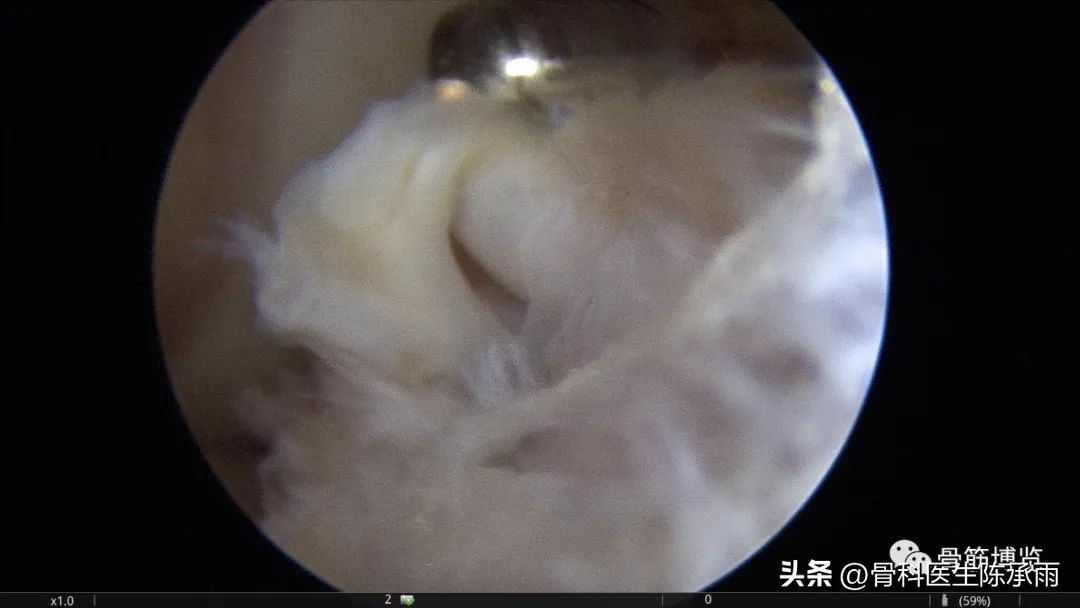

本例为内侧半月板前角巨大囊肿,关节镜下行半月板囊肿引流减压+囊肿前壁及囊壁滑膜切除+半月板缝合术。术中切除全部囊壁内滑膜及前壁及大部分后壁,保留部分后壁组织,以保证半月板前角缝合可靠及稳定。

术中情况